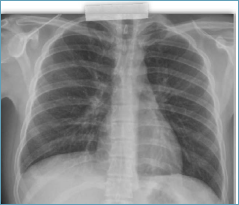

The patient showed rapid clinical improvement, with resolution of fever and hypoxaemia. Laboratory tests one week after corticosteroid initiation demonstrated reduced inflammatory markers but new-onset peripheral eosinophilia (3,130 eos/μL). Radiographic abnormalities progressively resolved (Fig. 3).

Figure 3.Chest X-ray. Minimal opacities in the lower third of the right hemithorax, with otherwise normal findings.